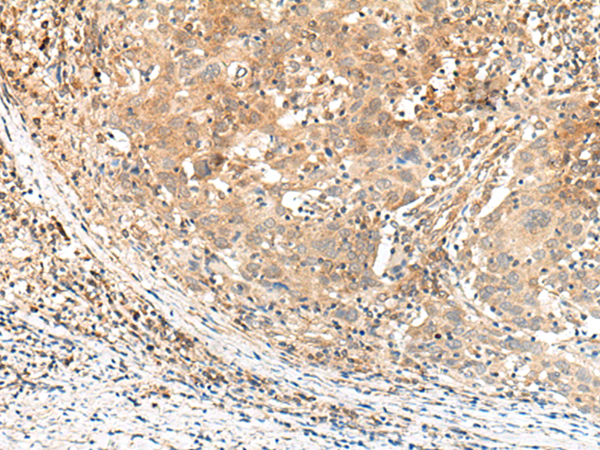

ELISA, IHC |

IHC positive control: |

Human cervical cancer |

IHC Recommend dilution: |

30-150 |